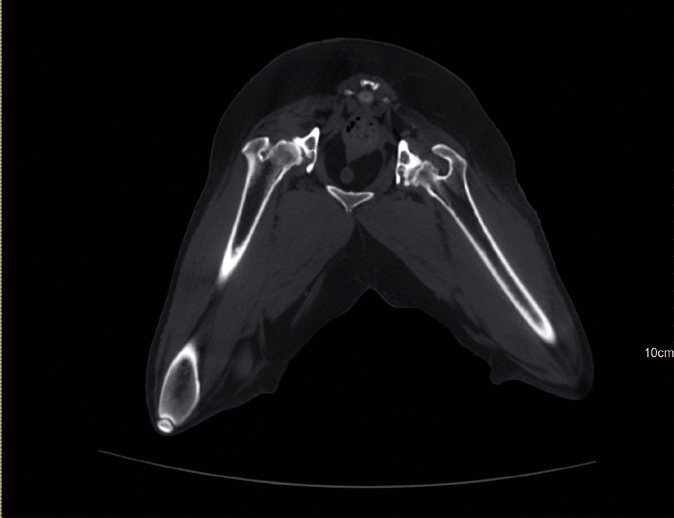

APLICAÇÕES CLINICAS